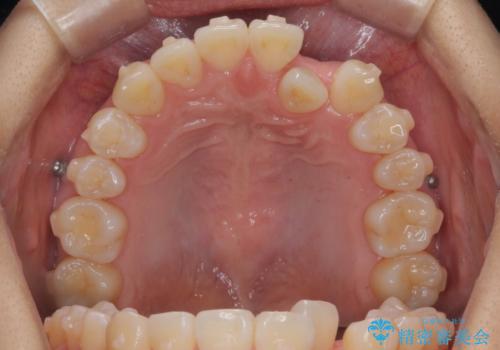

正中のズレ、引っ込んだ前歯の矯正

- 噛んだ時の前歯正中のズレ、引っ込んでいる前歯を治したい。と矯正治療を希望され来院されました。

左上2の前歯はスペースが足りないため、後方に引っ込んでしまっている状態です。

マウスピース矯正システムインビザラインで歯の後方移動、咬合関係の修正を行ったのち、引っ込んでいる左上2をワイヤーを用いて短時間で引き出す治療計画としました。

部分ワイヤー矯正を行なったことで約3ヶ月という短期間で前歯を綺麗に並べることができました。